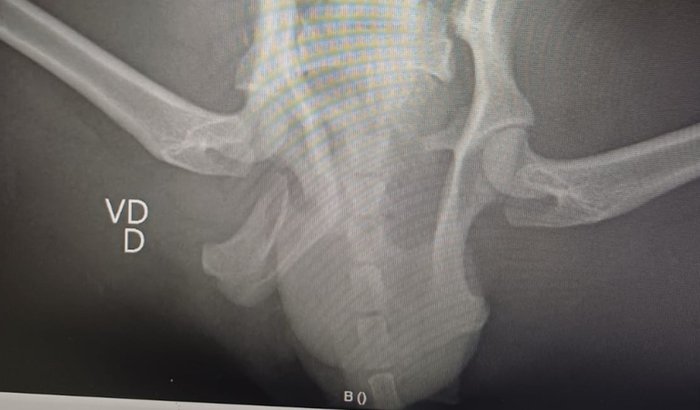

Infelizmente, doguinho da mjnha tia fugiu de casa e acabou sendo atropelado. Levamos ele correndo pro veterinário e agora estamos na luta com exames, cirurgia e medicação.